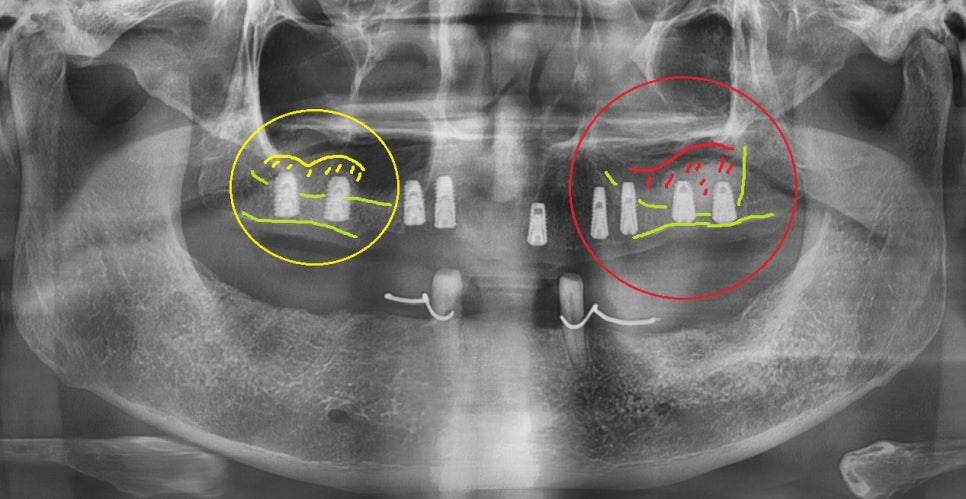

하악 CT의 경우 하치조 신경(붉은색 처리된 부분)과의

거리를 분석하여 신경손상이 거의 없도록

미리 예측하고 식립 합니다.

참고로 해당 과정이 잘못 될 경우 수술 과정 또는

수술 후의 출혈, 부종, 감염, 신경손상 등의

부작용이 발생할 수 있습니다.

우측 상악은 우선 수직 거상법을 활용하여

뼈 이식을 먼저 진행했습니다.

또한 좌측 상악 구치부의 경우에는

잔존골이 2mm정도 밖에 남아있지 않아서

난이도 높은 측방 거상법에 의해

치조골을 보충할 수 있는 뼈 이식 수술을 통해서

치조골의 양을 보충해 주는 치료를 진행했습니다.